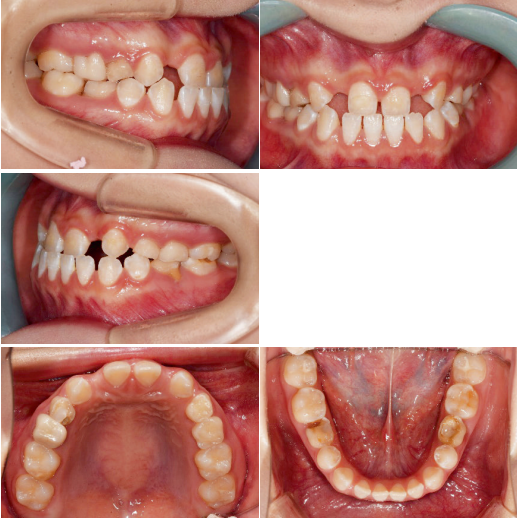

이 환자는 19세 여환으로 multiple congenitalmissing을 가지고 있으나 전치부 반대교합과 spacing의 해결만을 위해 내원하였습니다. 부분교정 시행후 상악 양측측절치 부위를 임플란트로 식립하기로결정하였습니다.

상악 양측 견치의 수직적 위치가 다른 것을 알 수 있습니다. 이는 추후 교정치료가마무리되면 전치부 교합평면의 canting이 확연히 보이게 되므로 문제가 될 수 있습니다.